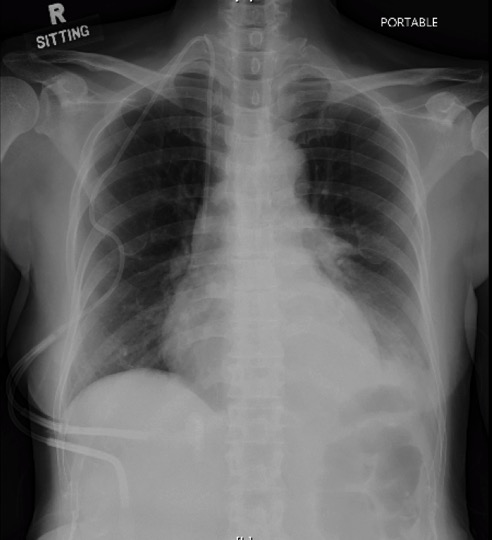

The antibiotic therapy was de-escalated to IV piperacillin/tazobactam on the third day of hospitalisation. However, she had a recurrence of fever on Day 4 of hospitalisation, associated with left-sided chest pain and breathlessness, requiring intra-nasal oxygen support (4 L/min). Her chest X-ray showed new left lower zone infiltrates (Figure 1 below) and she remained profoundly neutropenic at this point.